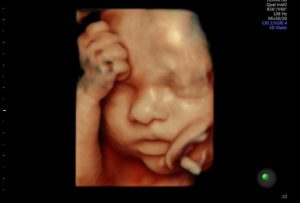

- ecografia ostetrica in 4D: osservazione tridimensionali del feto in tempo reale;